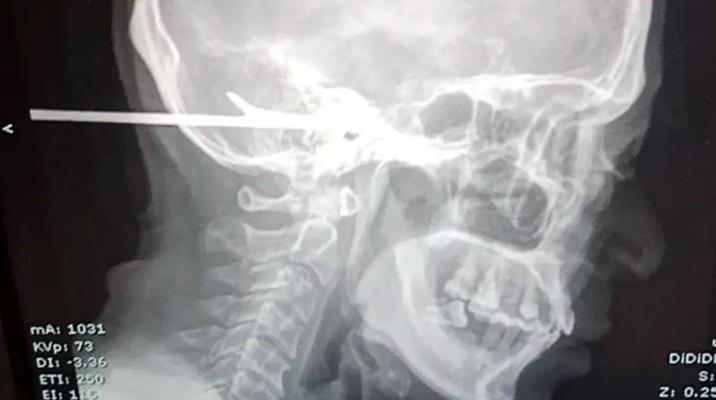

蘇吉特坐下來等候救援,後腦還插著魚叉(紅圈示)。(互聯網)

事發於本月3日,報道指,蘇吉特被魚叉插頭後意識清醒,還可以坐著,警員接報到場,隨後由友人們開車將蘇吉特送院。手術開始之前,醫護人員先使用工具把魚叉的長桿切掉,只留下最後數厘米。

蘇吉特需要接受X光和電腦掃描等詳細檢查,來評估腦部和頭骨的損傷情況。報道指,他並沒控告襲擊他的人。